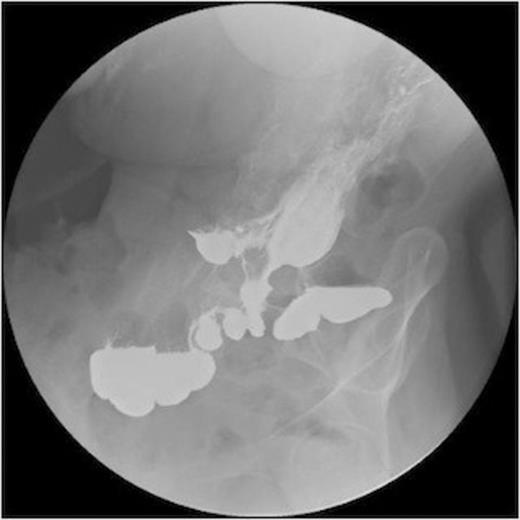

A series of radiographs from barium swallow demonstrating gastro-colic fistula